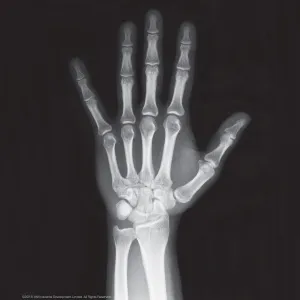

Анатомия – сложная область для изучения и запоминания, поэтому исследовательский набор «Скелет человека», с которым ребенок своими руками делает и собирает по схеме забавное украшение для дома – это лучший способ помочь ему познакомиться с основами строения человеческого организма. Родителям тоже будет интересно провести время с детьми за таким увлекательным занятием, а подробная инструкция и качественные материалы сделают процесс максимально удобным. Кроме того, в наборе есть рентгеновские снимки черепа, кисти и грудной клетки и настенная схема скелета в качестве дополнительных обучающих материалов для юного врача.

- Рентгеновские снимки – 3 шт.